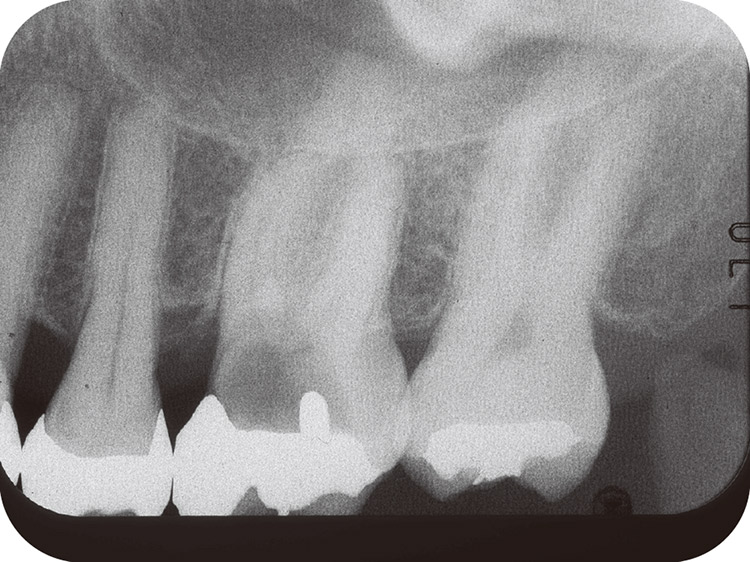

図4 7処置開始時のX線像。

図11 最終補綴処置時のX線像。